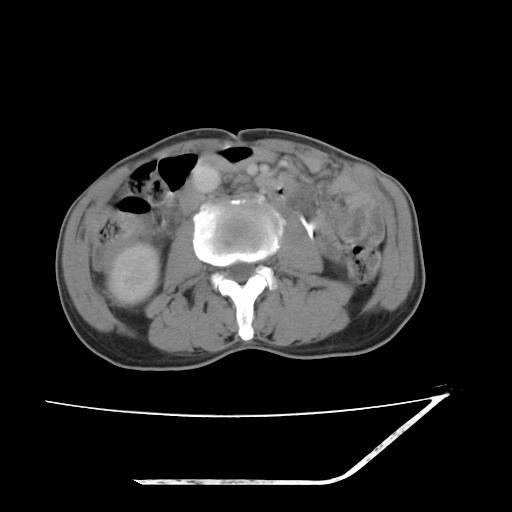

平扫

考虑右肾盂癌,肾动脉受侵,右肾功能减退,右肾盂输尿管积水,管壁增厚,考虑种植转移,应该把下面扫完的

支持右侧肾盂癌伴肾静脉瘤栓形成可能性大,右肾结石.肝右叶后段低密度影,不除外转移.

右肾盂旁ca并肾静脉瘤栓形成/肾功能降低。

右肾结石。

右肾盂癌,肾动脉受侵,右肾盂输尿管积水,管壁增厚,考虑种植转移

1.右侧肾盂癌伴肾盂积水。

2.肾脏功能减退,原因有:(1)肾动脉受侵。(2)肾静脉受侵(3)肾积水,等。本例,肾动脉显影较好,但受压明显;肾静脉无明显显示,受压或静脉癌栓,下腔静脉腔内未见明显充盈缺损。

3.右侧上段输尿管扩张,原因:(1)积水所致;(2)种植。